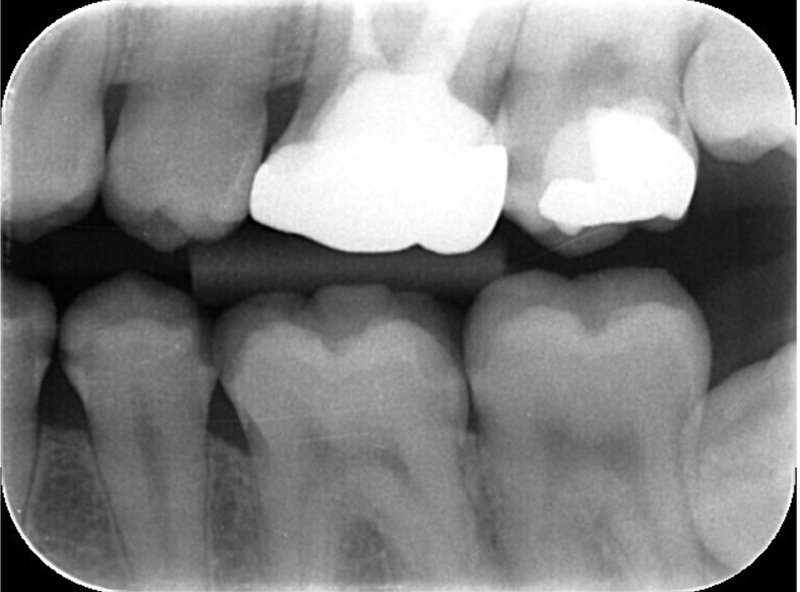

左下治療途中 左下レントゲン

治療途中 左下レントゲン レントゲン

年齢 23歳

性別 男性

治療部位 右下4・左下4・左下5

治療費 合計99,000円

ハイブリッドセラミックインレー33,000円×3本

(2023年1月現在)

治療期間 来院4回

リスク・副作用 天然の歯(強度:約400mpa)に比べて、ハイブリッドセラミックインレー(強度:270mpa)になり、強度では劣ります。

プラスティックを使用している特性上、着色がしやすいと言われています。

歯軋りや食いしばりの衝撃で一部欠けたり割れてしまう事がり、防ぐためにも就寝時に歯に装着するナイトガードの使用をおすすめいたします。

治療方針 虫歯検知液で染まった歯をペンスコープや口腔内写真を撮影し途中経過を患者様に説明をしながら進めています。

特記事項 歯ブラシでは届かない隣接面(歯と歯の間)は、虫歯になりやすい場所でもあるのでデンタルフロスの使用をおすすめします。

担当者所見 虫歯治療において、虫歯の取り残しがないか虫歯検知液(虫歯だけを青く染める薬液)を使い患者様への説明と確認をしながら治療を進めました。

ハイブリッドセラミックインレーの色も綺麗にあいました。